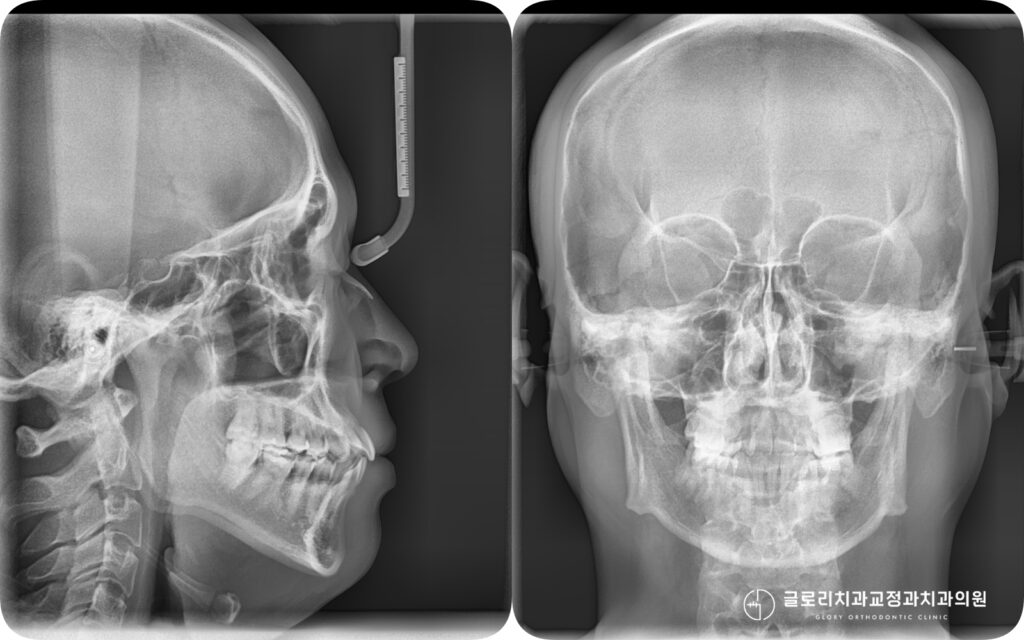

오늘은 총생과 정중선 편위가 동반된 부정교합을

상악골 확장장치를 활용한 비발치 교정으로 치료한 케이스를 소개드리려 합니다.

따라서 현재 좁은 치열궁의 공간을 넓혀주기 위해 상악골 확장장치를 적용한 비발치 교정을 선택합니다.